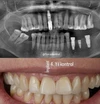

Fotoğraflar